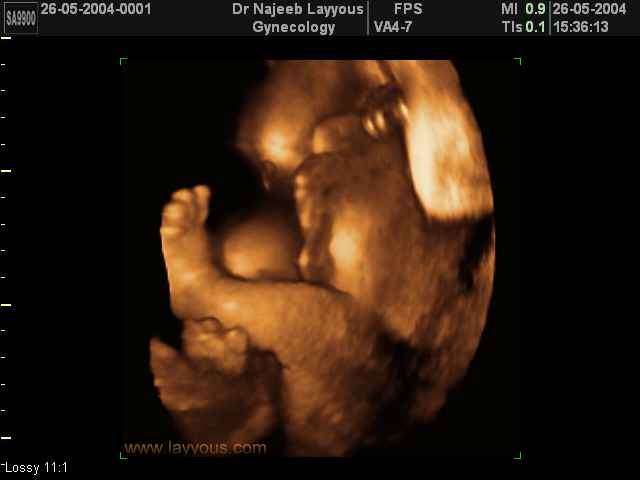

- لقطات فيديو للجنين بجهاز الموجات فوق صوتية رباعي الأبعاد

- صور لوجه الجنين في داخل الرحم

- صور لأطراف الجنين

- صور لتصرفات الجنين داخل الرحم